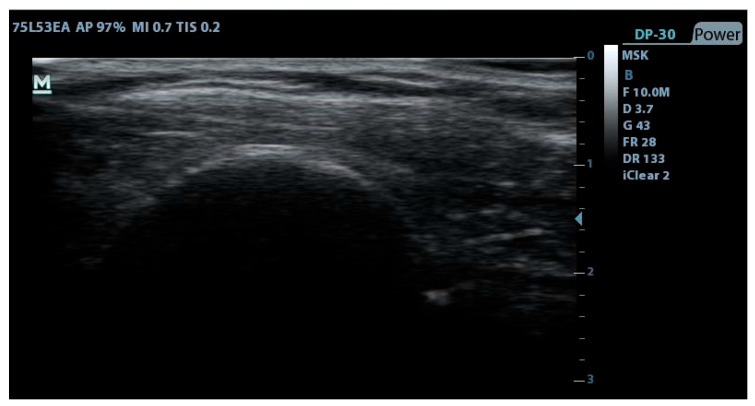

目的:本研究旨在探讨经皮电解法(PE)、经皮周围神经刺激法(PNS)和偏心运动法(EE)治疗冈上肌腱病变的疗效。方法:将46名冈上肌腱病变患者随机分配到有创治疗组(4周PE+PNS和EE治疗4次)和常规物理治疗组(10次,2周)。多模式物理方案包括超声治疗(US),经皮神经电刺激(TENS)和相同的EE方案。在基线、治疗结束、12周和24周随访时测量数值疼痛评定量表(NPRS)、肩关节活动度(ROM)、压痛阈值(PPT)和失能(DASH和SPADI)。结果:PE+PNS+EE组与TENS+US+EE组相比,在所有随访点(治疗后、12周和24周),PE+PNS+EE组在几乎所有疼痛、活动能力和功能结局方面均表现出更大且具有统计学意义的改善,通常具有中等到较大的效应量。结论:本研究得出PE+PNS+EE联合干预是冈上肌腱病变安全有效的治疗方法,与传统电疗相比,在疼痛、活动能力和功能方面有统计学意义的改善。

Objectives: This study aimed to investigate the efficacy of Percutaneous Electrolysis (PE), Percutaneous peripheral Nerve Stimulation (PNS), and Eccentric Exercise (EE) in patients with supraspinatus tendinopathy. Methods: Forty-six participants with supraspinatus tendinopathy were randomly allocated to either an invasive therapy group (four sessions in four weeks of PE+PNS and EE program) or a conventional physical therapy group (ten sessions for 2 weeks). The multimodal physical program included Ultrasound therapy (US), Transcutaneous Electric Nerve Stimulation (TENS) and the same EE program. The Numerical Pain Rating Scale (NPRS), shoulder Range of Motion (ROM), Pressure Pain Threshold (PPT), and disability (DASH and SPADI) were measured at baseline, at the end of treatment, and at 12- and 24-weeks follow-up. Results: The PE+PNS+EE group demonstrated consistently greater and statistically significant improvements across nearly all pain, mobility, and functional outcomes at all follow-up points (post-treatment, 12-weeks, and 24-weeks) compared to the TENS+US+EE group, with generally medium to large effect sizes. Conclusions: This study concludes that the combined PE+PNS+EE intervention offers safe and effective treatment for supraspinatus tendinopathy, demonstrating statistically significant improvements in pain, mobility, and function compared to conventional electrotherapy.